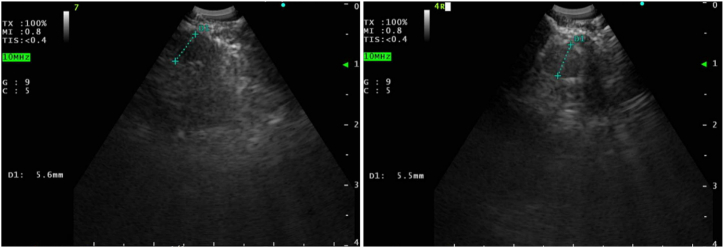

结节病是一种罕见的慢性肉芽肿性疾病,病因不明。心脏结节病(CS)的明确诊断尤其困难。有几种诊断CS的指南,但尚未得到临床验证。尽管心肌膜活检具有高特异性,但其敏感性低,潜在并发症的严重程度高。因此,我们报告63岁男性,经支气管超声(EBUS)经支气管针吸(TBNA)胸内淋巴结诊断为CS,该淋巴结未扩大,无PET可见性。影像学上表现正常的淋巴结EBUS - TBNA显示非坏死性肉芽肿。鉴于CS诊断的挑战,即使在没有明显活动性肺结节病证据的病例中,也可以考虑EBUS TBNA。

Sarcoidosis is a rare chronic granulomatous disease with unknown etiology. Definite diagnosis of cardiac sarcoidosis (CS) is especially difficult to establish. Several guidelines exist to make a diagnosis of CS but those have not been clinically validated. Despite the high specificity of endomyocardial biopsy, its sensitivity is low, and the severity of potential complications is high. Thus, we present 63-year-old male who was diagnosed with CS with the endobronchial ultrasound (EBUS) transbronchial needle aspiration (TBNA) of intrathoracic lymph nodes which were non-enlarged without PET avidity. EBUS TBNA of radiographically normal appearing lymph nodes showed non-necrotizing granulomas. Given challenges of diagnosing CS, EBUS TBNA can be considered even in cases without obvious evidence of active pulmonary sarcoidosis.